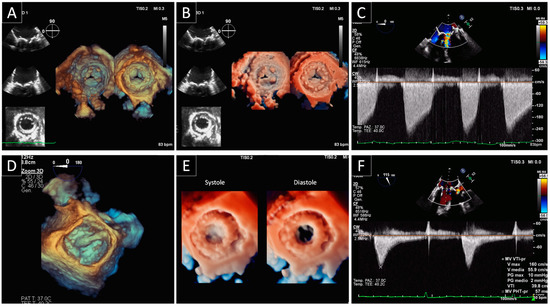

4. Bioprosthetic Structural Valve Degeneration

4.1. Mitral Bioprosthetic SVD

4.2. Aortic Bioprosthetic SVD